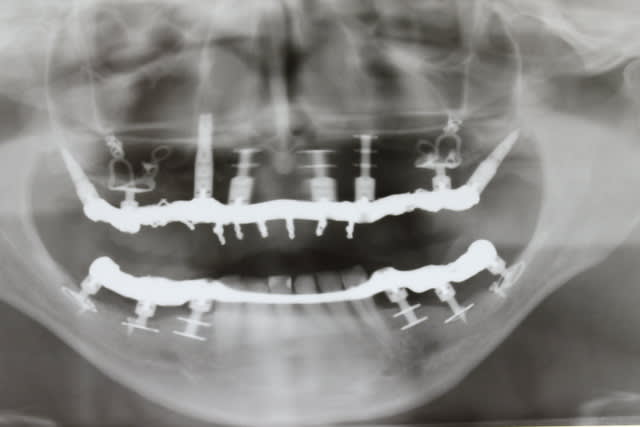

Les plaques existent depuis environ une dizaine d années

Je suis un des tous premiers à en avoir posé en dehors de GS puisqu à l époque il m en a confié une pour poser à la mandibule chez une patiente où je n avais pas pu poser un monodisk

J ai posé cette plaque en quais totalement enfoui à l époque : elle tjs là totalement indolore, bien sonore comme un cylindre

Je vais te filer qques photos d une patiente opérée voici 3 ans avec du nano et des plaques rien que l aspect de la muqueuse te montrera que tout ça est sain et ossifié

Le volume est en effet bien plus grand après, mais je me permet d'avoir quelques doutes sur l'intégration des plaques au niveau osseux...reste à avoir des études et des statistiques sur quelques centaines de cas, voir plus ;-)

Par contre je peux te dire que les 4 plaques et même le monodisk sont sonores et parfaitement indolores donc a priori intégrés béton